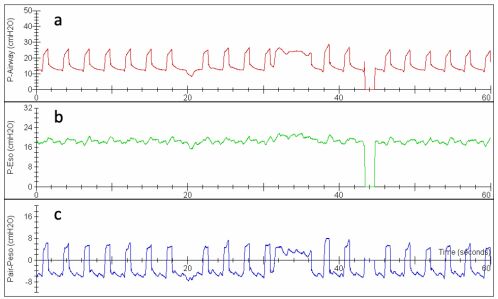

53. 下圖為一位 ARDS 病人 airway(a),esophageal(b) pressure tracing,及其相減的圖形 (c),何者正確? (A) 在吐氣時,transpulmonary pressure 約為 4 至 6cmH2O。 (B) 根據 tracing,可以考慮增加 PEEP,以改善 atelectasis。 (C) 可以考慮進一步減少 tidal volume,避免 ventilator-induced lung injury(VILI)。 (D) 根據 tracing,PEEP 大約為 18cmH2O。